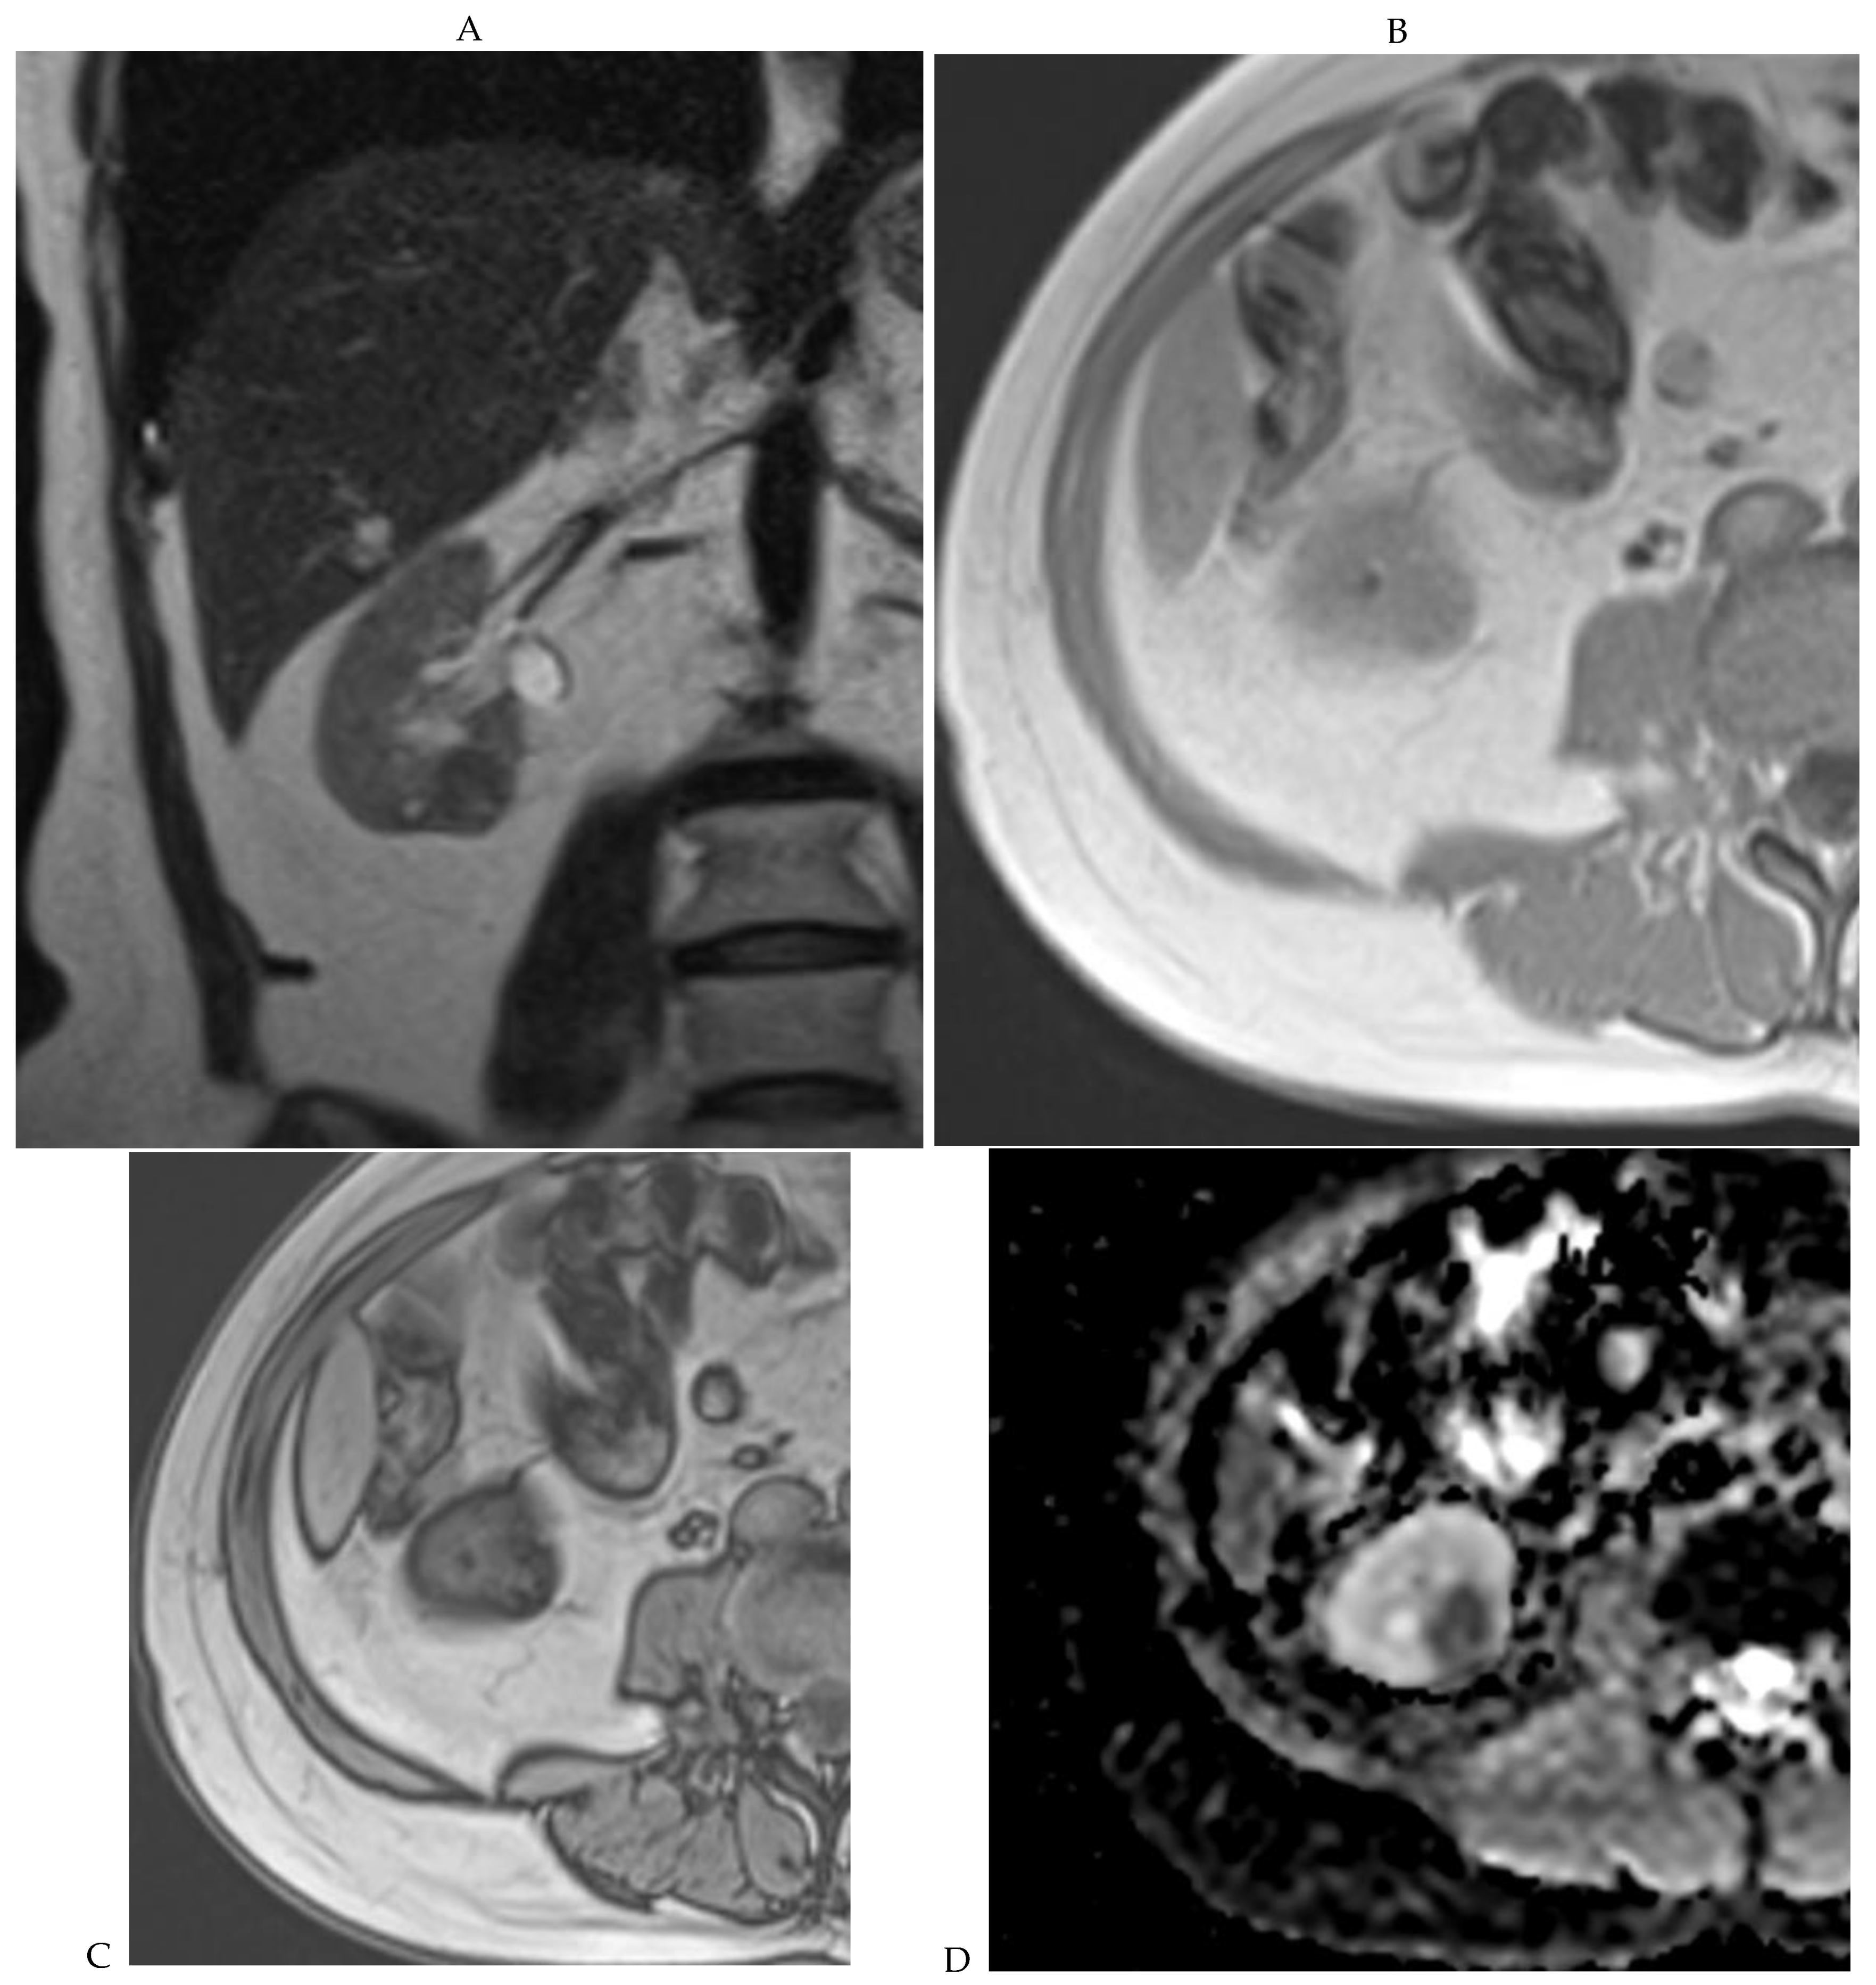

Figure 6.

Fat-poor angiomyolipoma in the right kidney of a 46-year-old-man. (A) Coronal T2-weighted fast SE image shows the low signal intensity of the lesion compared with the renal parenchyma. Transverse in-phase (B,C) opposed-phase MR images show a significant loss of signal intensity on the opposed-phase image. (D) The ADC map shows marked restriction of tumor diffusion into the renal mass. Transverse gadolinium-enhanced T1-weighted gradient-echo spoiled MR images in (E) corticomedullary, (F) nephrographic, (G) and delayed phase images show early enhancement and rapid washout.